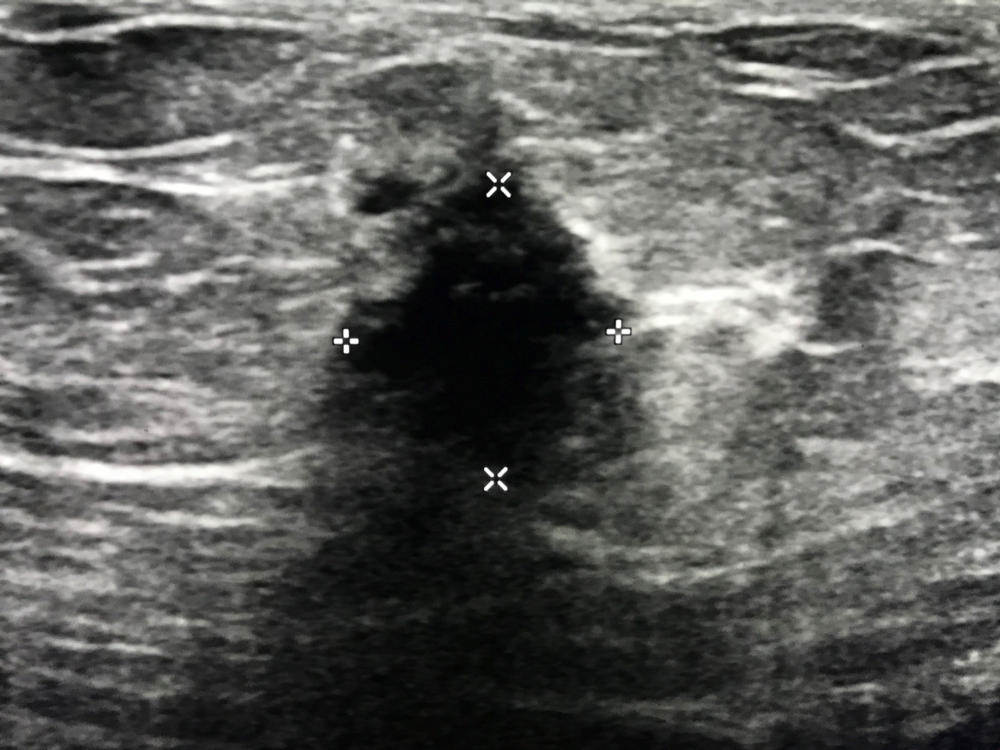

Figure 3. Ultrasound image of the breast after ablation demonstrates the very visible black "ice ball" completely engulfing the cancer (outlined by +).

High-res (TIF) version